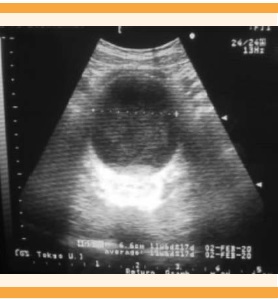

El ultrasonido pélvico reportó: ovario derecho con imagen anecoica heterogénea, turbia, con sedimento en su base, de 76 x 74 mm (Figura 1). Con estos hallazgos se estableció el diagnóstico de quiste de ovario. En la laparotomía exploradora se encontraron: útero y ovarios normales, abultamiento en el hueco pélvico retroperitoneal, que protruía el útero hacia arriba y lo envolvía en toda su periferia. En el posoperatorio, la tomografía evidenció una imagen piriforme de gran tamaño (13 x 9 cm) en la zona abdominopélvica, hipodensa, debidamente delimitada, que desplazaba el útero hacia arriba y hacia la derecha, y se comunicaba con la cavidad uterina dilatándola. La exploración física minuciosa reportó: himen a tensión (Figura 2). Con estos datos se integró el diagnóstico de himen imperforado y hematocolpos.